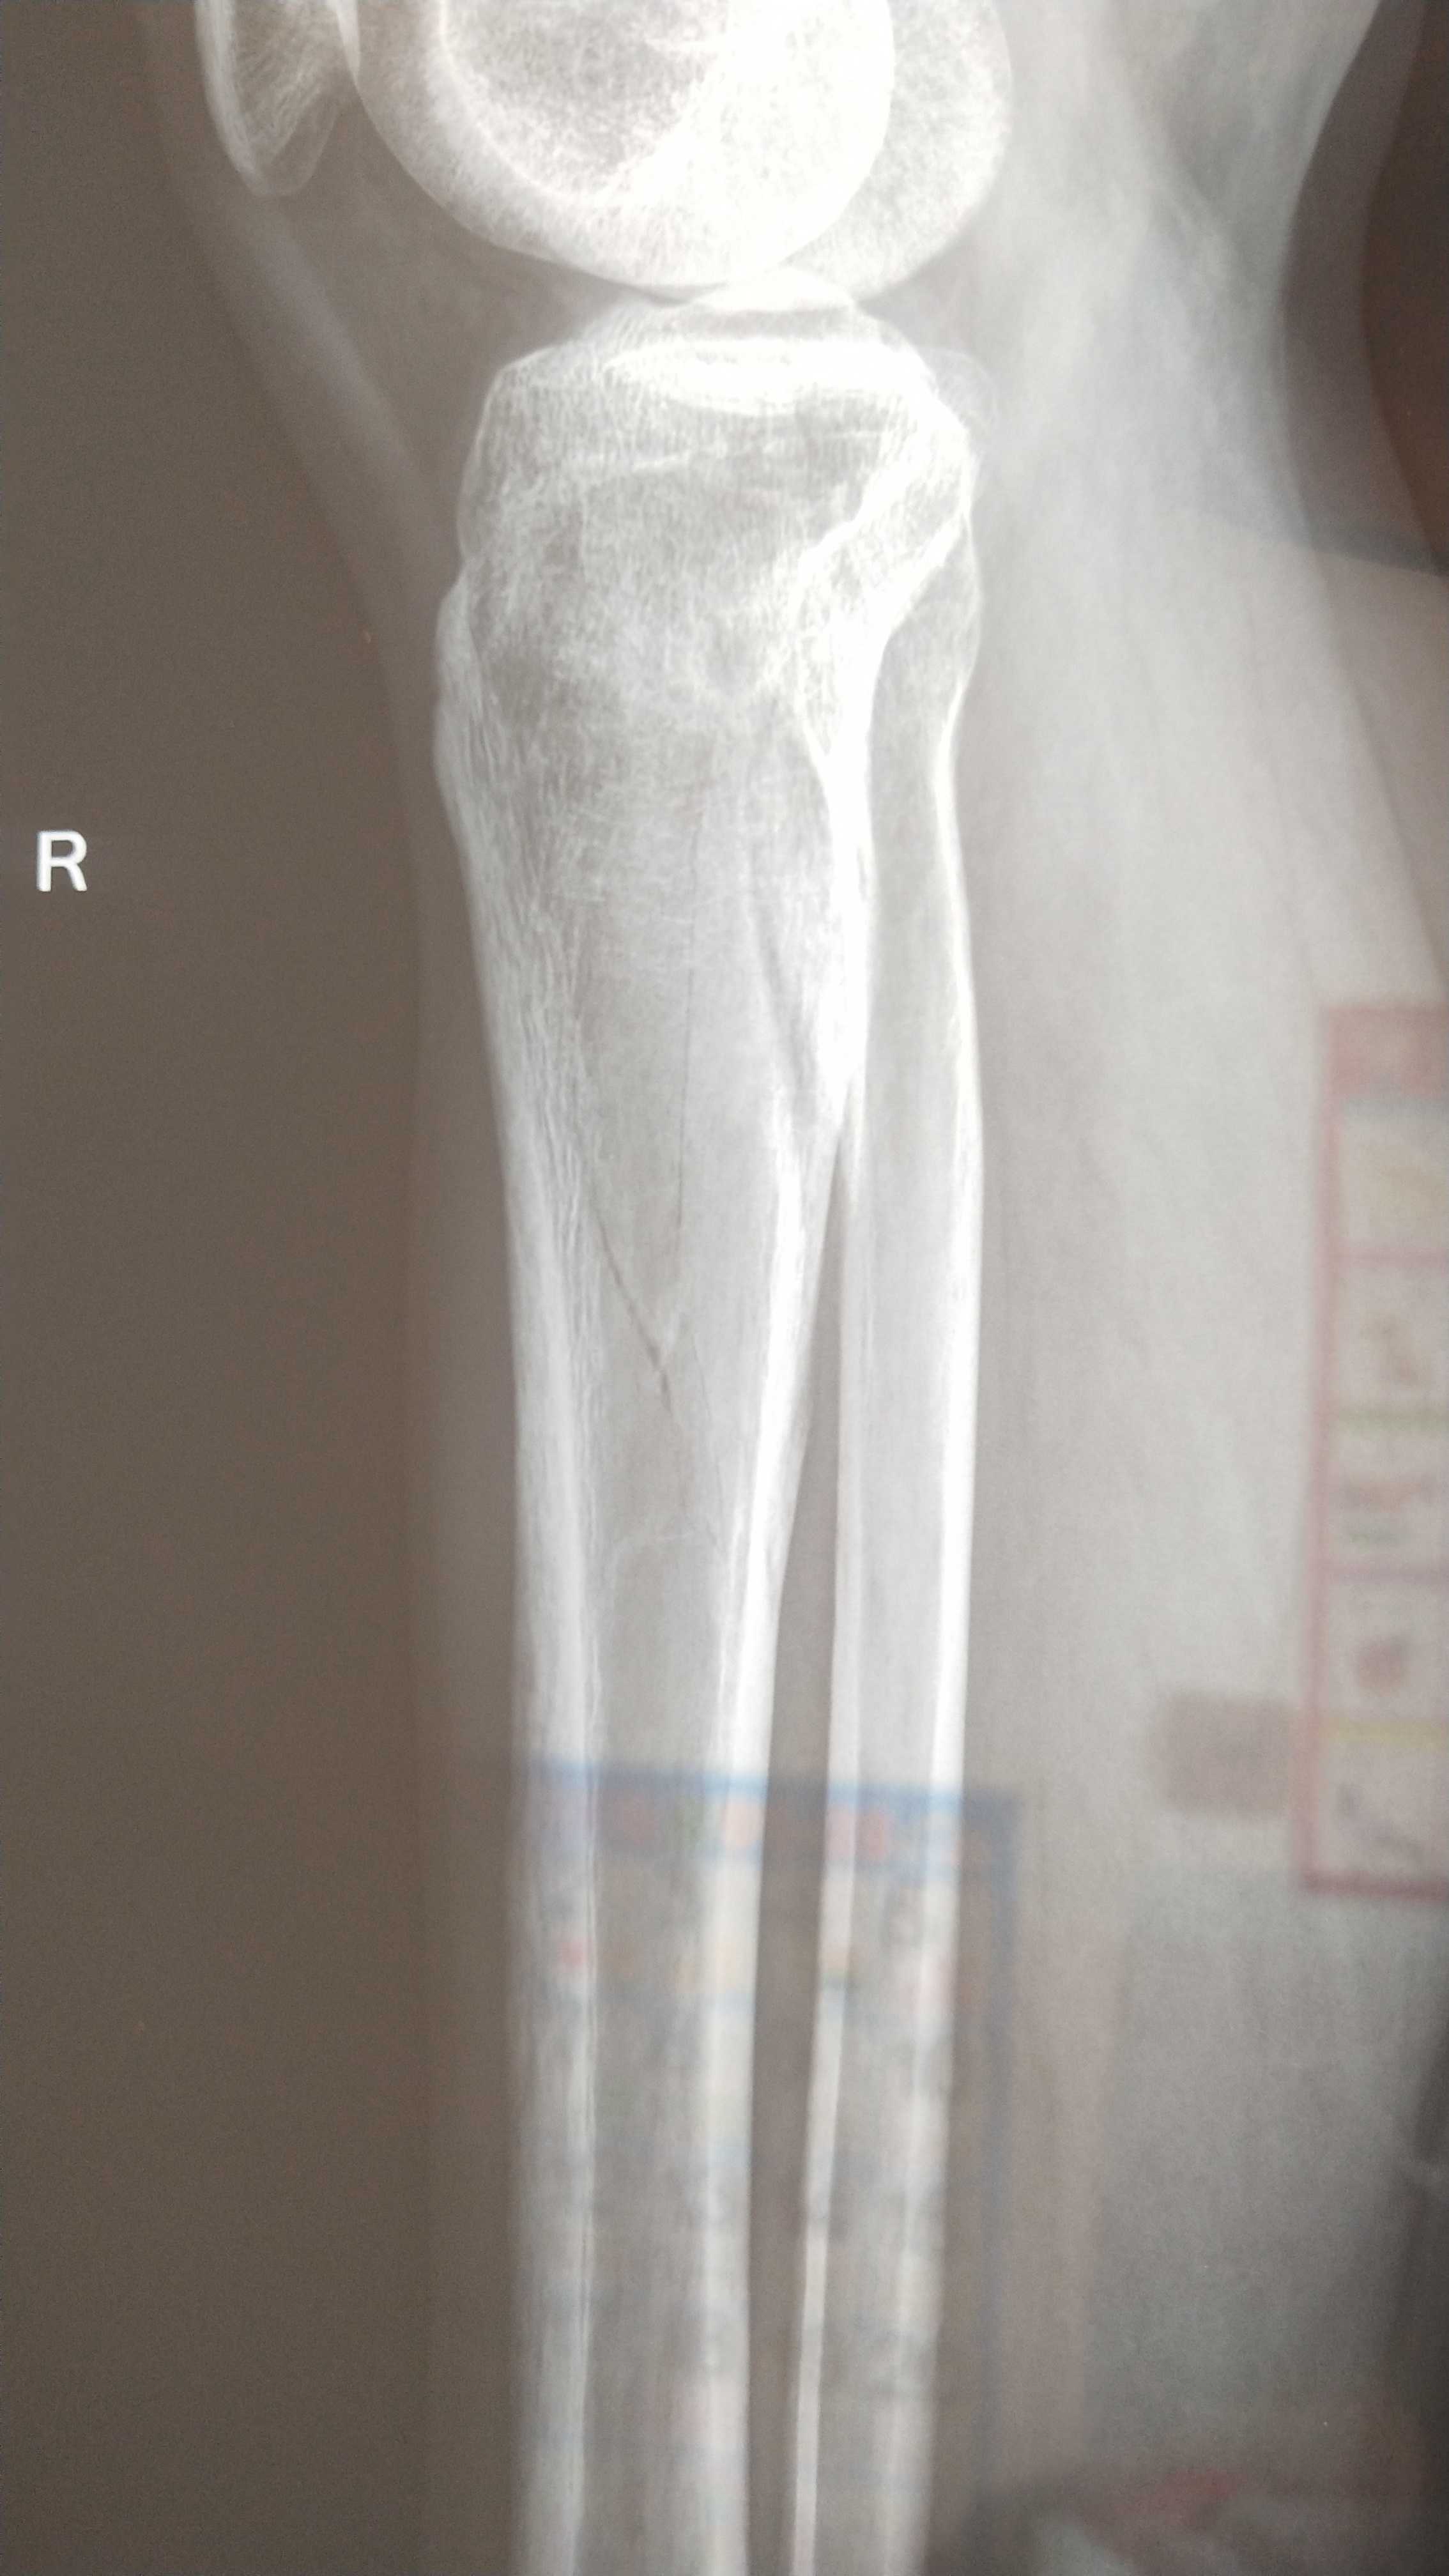

2019年12月19号受伤至今已经150天,是被重物砸伤,拍片检查胫骨平台粉碎性骨折,我也自己老了片子确实裂了好几道口子,医生建议手术治疗,手术目的是固定骨折部位提前解放关节防止后期出现关节粘连。

从车站出来家人陪我去了当地人民医院拍片检查,防止长途颠簸出现严重的二次伤害,好在片子出来后问题不大,医生也说可以保守治疗,回家慢慢修养,定时拍片检查。

后来疫情可控后又去医院拍了两次片子,80天的那次腿部出现了血栓,骨折线稍模糊 开了两盒治疗血栓进口药,140天的时候检查血栓没有了但是有了骨质疏松,骨折线稍模糊。